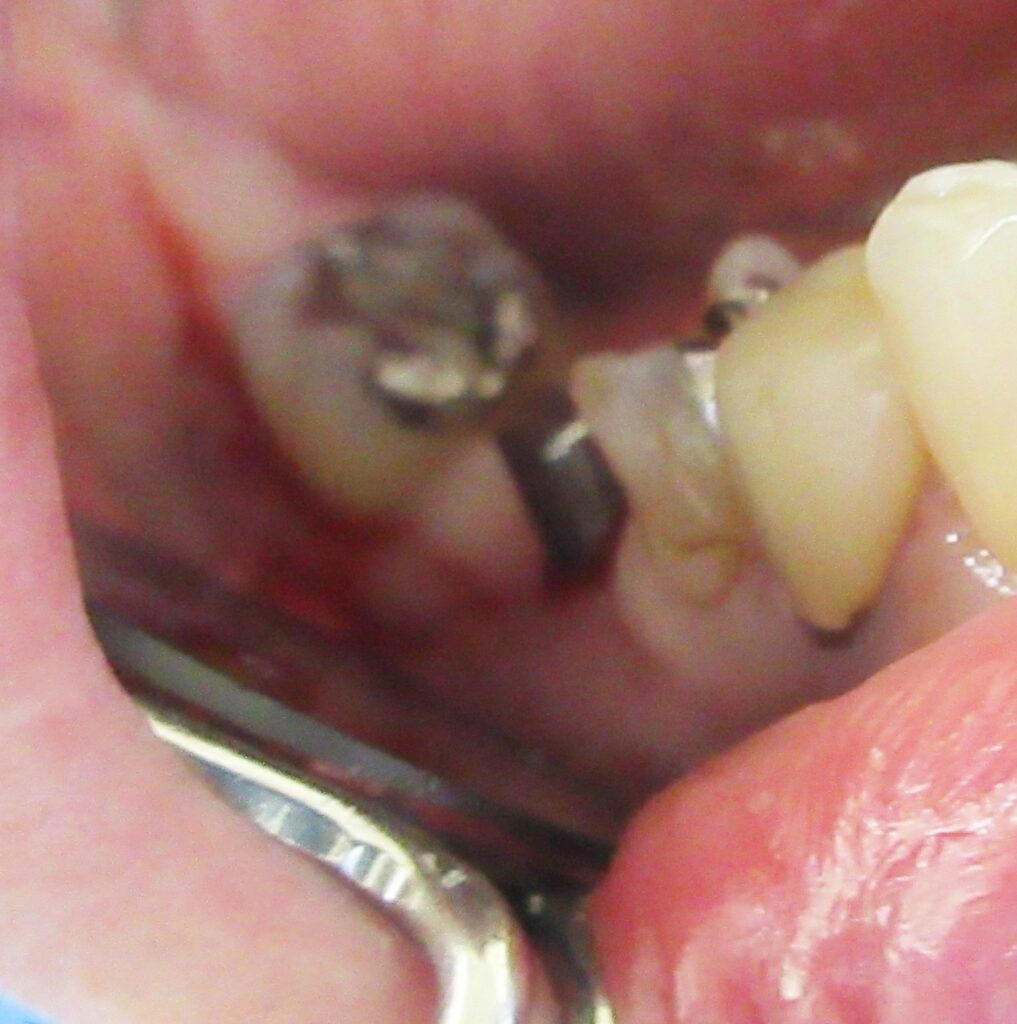

くりぬいた部分の歯肉を取り除き、次は骨に穴を開けていきます。

ドリルの先端を細い物から徐々に大きい物に変えながら、植立するインプラント体のネジの部分を除いた胴の部分の太さに合わせた大きさの穴を開けていきます。

開けた穴に、専用道具を使ってネジを締めるように長さ2センチ程のインプラントを骨に埋め込んでいきます。